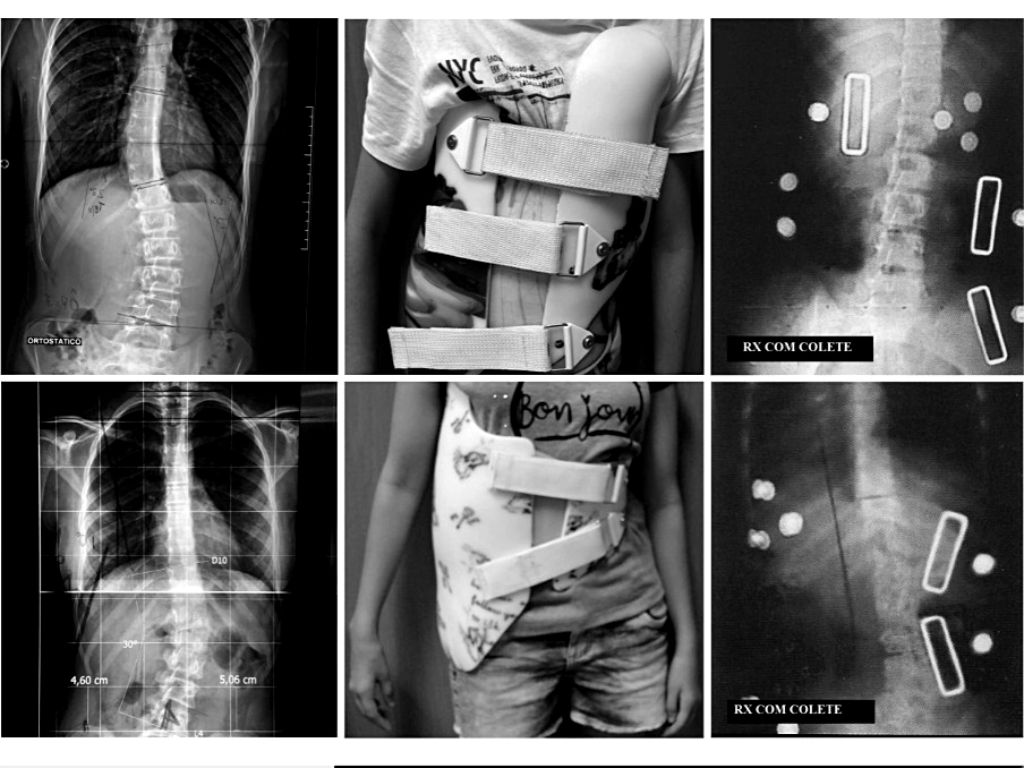

Coletes para

Escoliose

Coletes ortopédicos projetados para o tratamento e controle da escoliose, helping na correção postural e na estabilização da coluna vertebral.